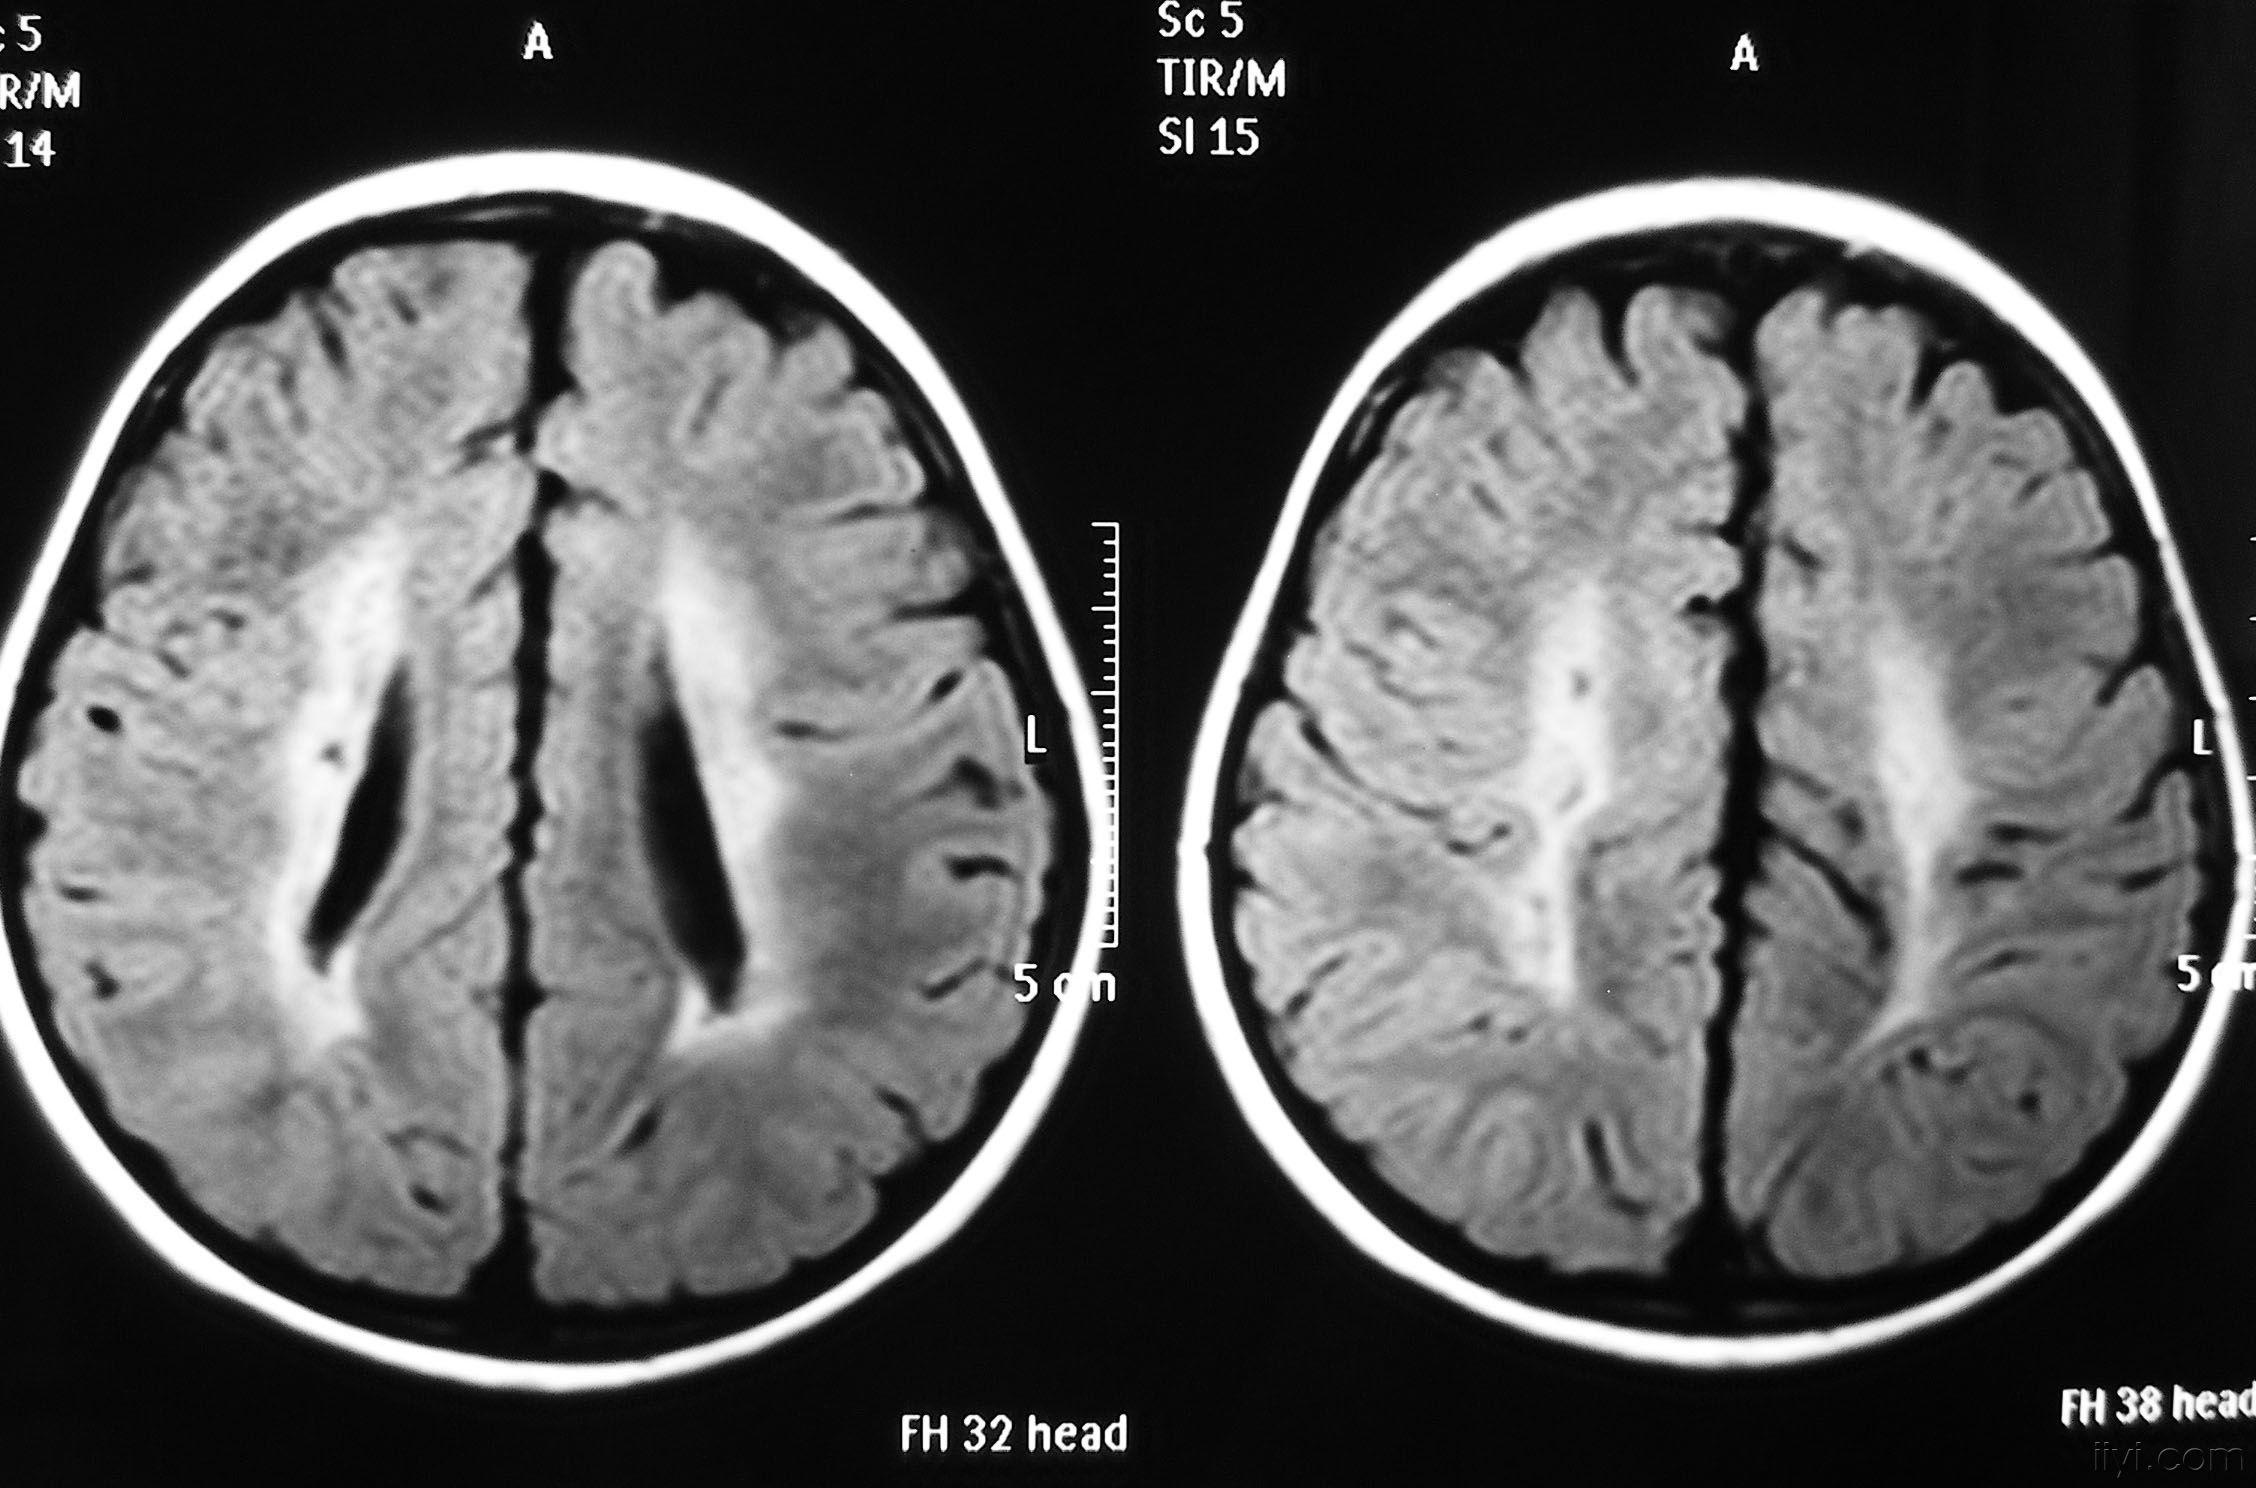

影像学发生于侧脑室周围,侧脑室扩大,脑白质减少。扩大的侧脑室外缘常不规则为其特点,多为双侧脑室同时扩大。脑白质减少,脑皮层与脑室侧缘相近。MRI T1呈低信号,T2呈高信号。